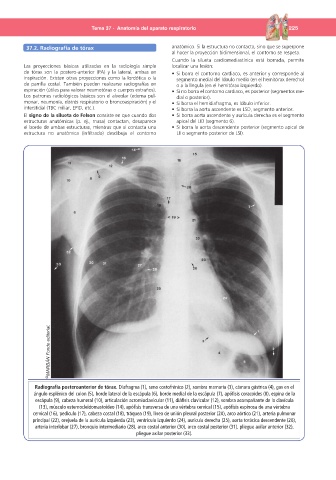

Radiografía posteroanterior de tórax. Diafragma (1), seno costofrénico (2), sombra mamaria (3), cámara gástrica (4), gas en el

ángulo esplénico del colon (5), borde lateral de la escápula (6), borde medial de la escápula (7), apófisis coracoides (8), espina de la

escápula (9), cabeza humeral (10), articulación acromioclavicular (11), diáfisis clavicular (12), sombra acompañante de la clavícula

(13), músculo esternocleidomastoideo (14), apófisis transversa de una vértebra cervical (15), apófisis espinosa de una vértebra

cervical (16), pedículo (17), cabeza costal (18), tráquea (19), línea de unión pleural posterior (20), arco aórtico (21), arteria pulmonar

principal (22), orejuela de la aurícula izquierda (23), ventrículo izquierdo (24), aurícula derecha (25), aorta torácica descendente (26),

arteria interlobar (27), bronquio intermediario (28), arco costal anterior (30), arco costal posterior (31), pliegue axilar anterior (32),

pliegue axilar posterior (33).